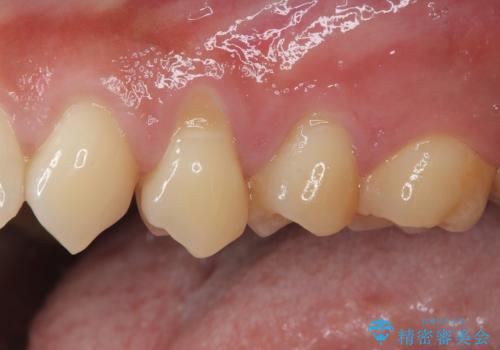

冷たいものがしみる 歯肉移植術で根面被覆